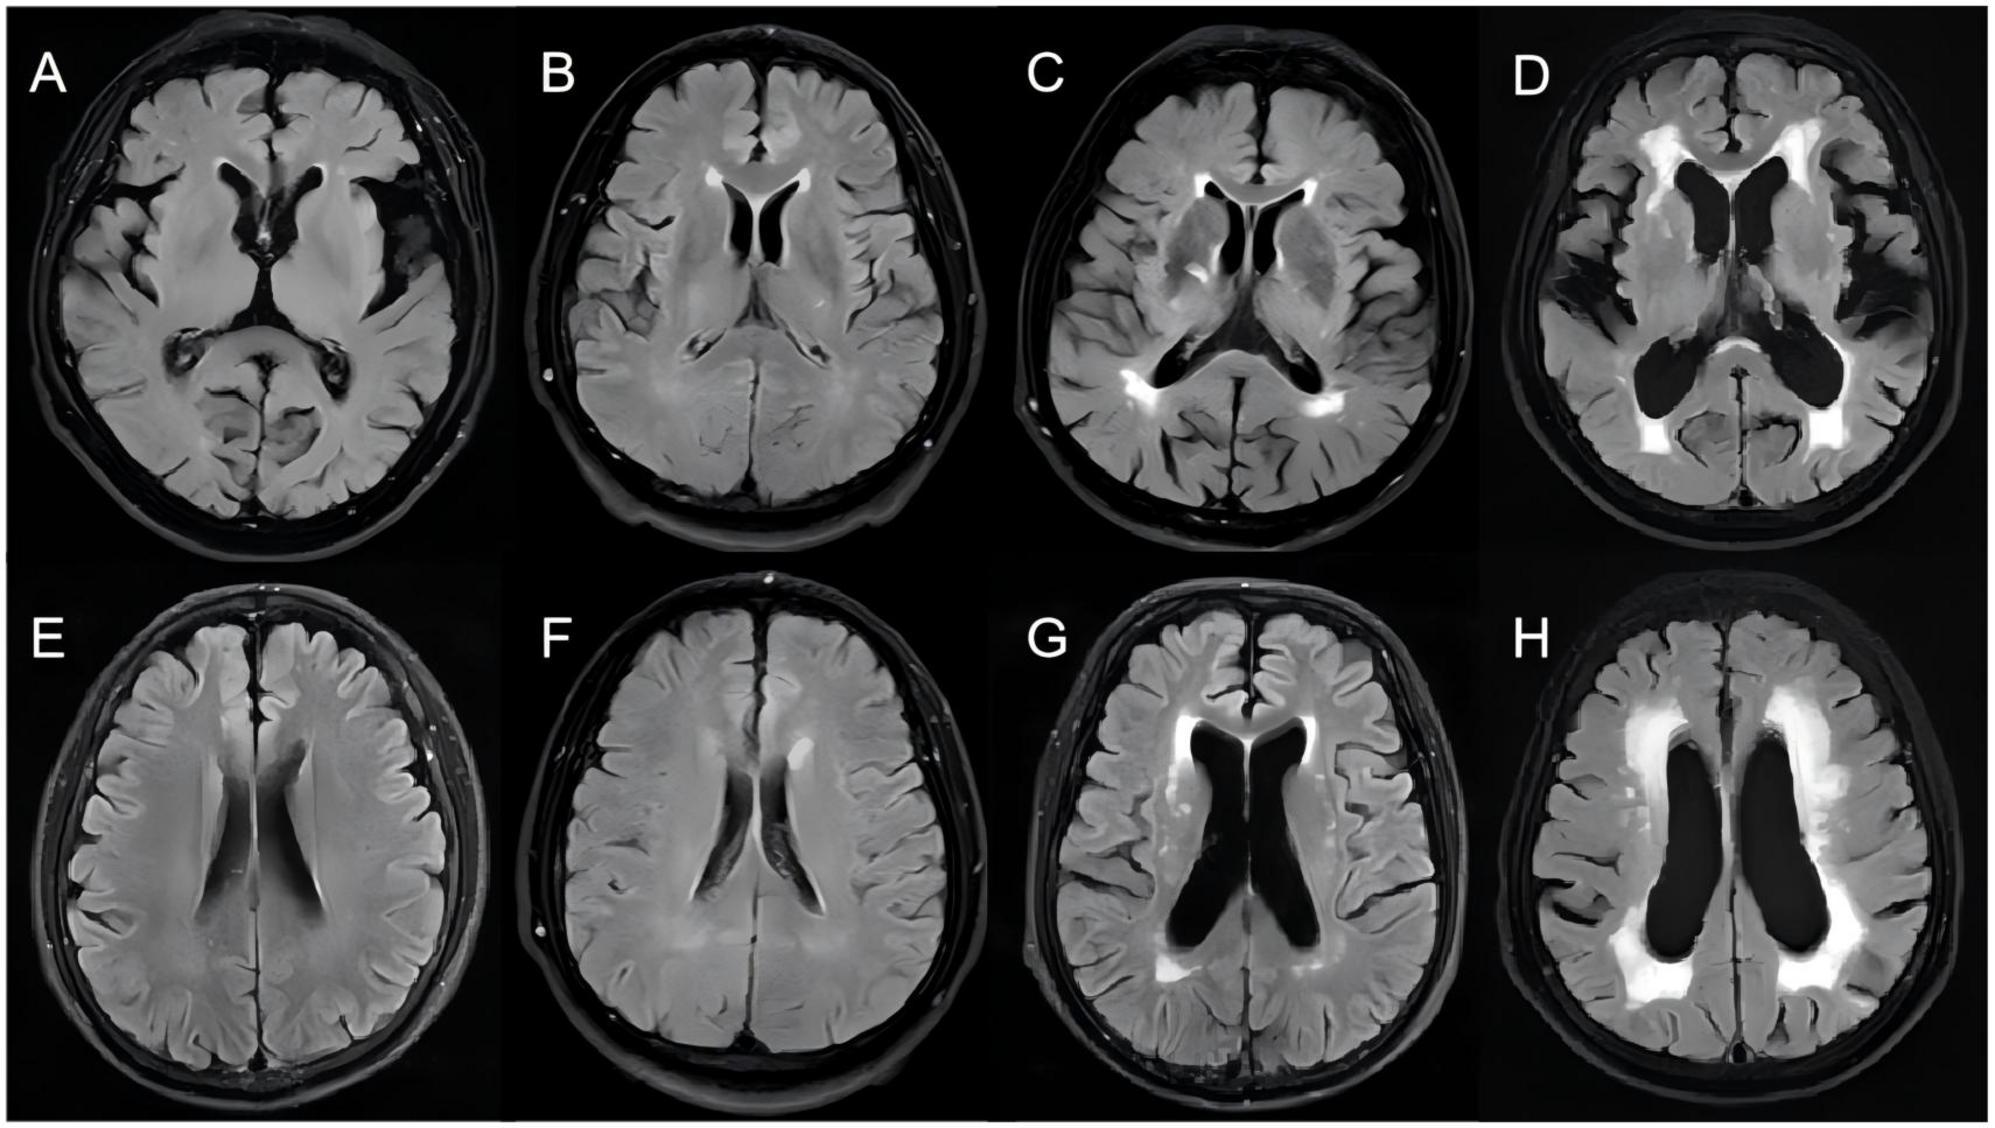

Background: White matter hyperintensity (WMH), a common neuroimaging feature in the older adults, has not been systematically elucidated regarding its association with cognitive function and systemic inflammation. Aim: To develop and validate a clinical model for higher WMH burden integrating MoCA and CBC-derived inflammatory markers, and to quantify their independent and joint associations with WMH severity.Methods: This study retrospectively collected data from patients with WMH at the First Affiliated Hospital of Baotou Medical College (December 2023 - December 2024).We used univariate and multivariate logistic regression analyses to identify WMH-related variables. Then, we constructed an artificial neural network model and performed Ten-fold cross-validation for internal validation and model performance comparison.The Shapley Additive Explanations (SHAP) method was employed to evaluate both models.Results: Correlation analysis revealed a significant association between the systemic inflammation response index (SIRI) and WMH burden (P < 0.01). Multivariate logistic regression analysis identified age, hypertension, high-density lipoprotein (HDL), previous cerebrovascular disease, the systemic inflammation response index (SIRI), and the Montreal Cognitive Assessment (MoCA) score as independent predictors of WMH burden.Ten-fold cross-validation showed that the set neural network model performed as well as the logistic regression model (AUC=0.824). SHAP-based visual analysis identified age, MoCA score, and hypertension as key driving factors.Conclusion: Age, hypertension, previous cerebrovascular disease, HDL, SIRI and MoCA score are independent risk factors for moderate to severe WMH occurred.The model integrating MoCA and inflammatory markers accurately predicts moderate to Severe WMH. This study offers a multidimensional assessment framework for WMH risk stratification and early intervention.